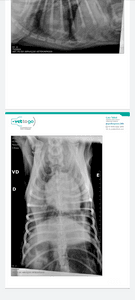

O spike foi atropelado foi atropelado  em quanto passeava, o motorista  nos prestou socorro mas logo foi embora ele teve grave fraturas no tórax  está com pneumotórax e hemorragia pulmonar. E precisa ficar entubado com intervenção  de ventilação mecânica e analgesicos  nessecita  de uma tomografia e medicamentos para estabilizar o quadro pulmonar ele precisa ficar internado por no mínimo 72h e fazer exames de rx diários para acompanhar seu quadro cada diária com aparelho medicação  e exame está 2.710 eu estou desempregada e só  meu esposo está trabalhando tenho uma filha de 6 anos que estava no momento  do acidente els esta tendo febre desde tarde não come e não está conseguindo  dormir direito passou o dia todo chorando  por causa do cachorro. Estou desesperada não sei mais oque fazer peço pelo amor de Deus  que vcs nos ajudem com o tratamento  do spike que Deus os abençoe  grandemente. #forçaspike

As 2 h da manhã o médico me enviou msg pois o Spike deu uma piorada eles precisam realizar uma tomografia para ver melhor o tamanho da lesão e fazer a drenagem do sangue que está no pulmão. Eles só liberam exames e medicames diante o pagamento o Spike está recebendo anestesia pelo soro para reduzir as dores